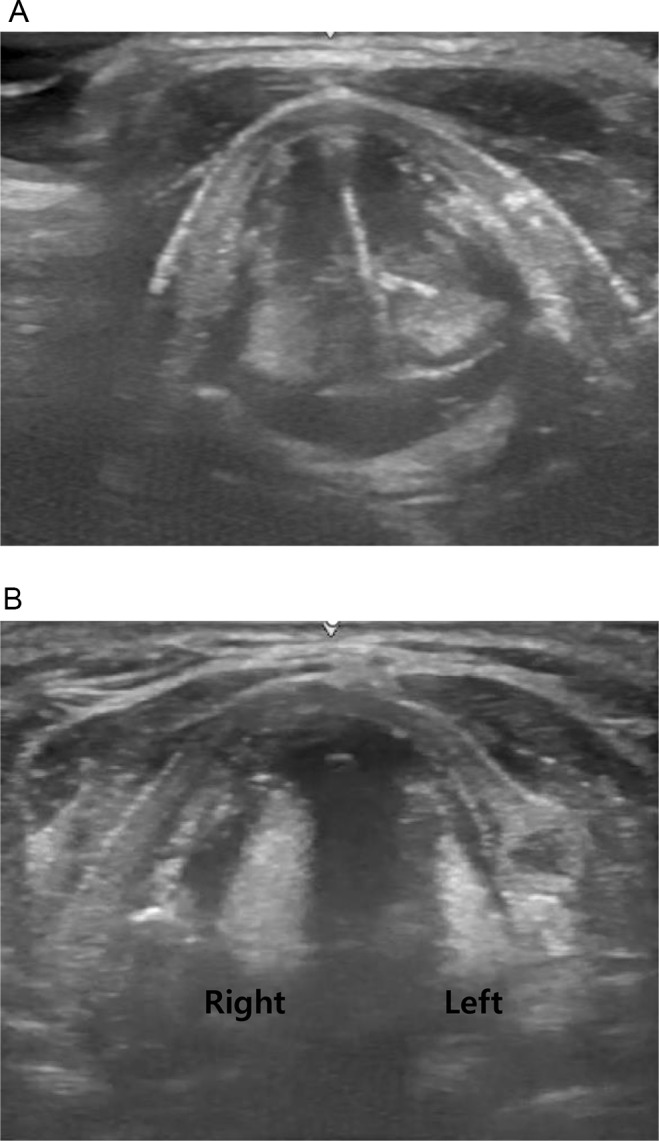

重症监护病房(ICU)患者缺乏早期吞咽功能评估工具可能会导致口腔摄入延迟。本研究评估了一种新型床旁吞咽筛查工具在检测重症监护室或隔离环境中患者吞咽困难方面的有效性。我们对 13 名重症急性呼吸窘迫综合征患者的吞咽功能进行了评估。为确保患者安全,我们在床边进行了初步调查,以评估患者的警觉程度,并获得了声带超声波检查结果。如果患者未达到一定的准备水平,则对其进行鼻胃管喂养或禁食。此外,通过初步调查的患者还将分别接受亚甲蓝染料或柠檬酸吞咽测试,如果他们接受或未接受气管造口术的话。Gugging 吞咽筛查(GUSS)测试用于确定是否适合口服饮食。在 13 名患者中,1 人在初步检查中不符合标准,12 人接受了检查并开始口服饮食。气管造口术组和非气管造口术组的 GUSS 评分有显著差异,但检查有效性无显著差异。如果在每个阶段均未达到检查标准,则实施 NG 插管。通过新开发的吞咽困难筛查工具的患者在开始口喂后没有出现吸入症状,因此可以出院。总之,所建议的筛查测试可以安全、简便地进行,从而早期发现吞咽困难,降低吸入风险,并确保重症监护室或隔离环境中患者的口腔喂养安全。

The lack of early assessment tools for swallowing function in patients in the intensive care unit (ICU) may lead to delays in oral intake. This study assessed the effectiveness of a new bedside swallowing screening tool in detecting dysphagia in patients in the ICU or isolation settings, where isolation settings refer to conditions such as COVID-19, where patient mobility is limited. We assessed swallowing function in 13 patients with severe acute respiratory distress syndrome. To ensure patient safety, a bedside preliminary investigation was performed to assess the patient's alertness level, and ultrasound findings of the vocal cords were obtained. Patients were nasogastric(NG) tube feeding or fasted if they did not meet a certain readiness level. Additionally, patients who passed the preliminary investigation underwent methylene blue dye or citric acid swallowing tests if they had or had not undergone tracheostomy, respectively. The Gugging Swallowing Screen (GUSS) test was used to determine whether an oral diet was appropriate. Of the 13 patients, 1 failed to meet the criteria during the preliminary examination, and 12 underwent the examination and initiated oral intake. Significant differences were found in the GUSS scores between the tracheostomy and non-tracheostomy groups but not in the examination validity. NG tube was implemented if the examination criteria were not met at each stage. Patients who passed the newly developed dysphagia screening tool exhibited no aspiration symptoms post-oral feeding initiation, enabling their discharge. In conclusion, the proposed screening test can be performed safely and easily, allowing for early dysphagia detection, reduced aspiration risk, and safe oral feeding in patients in the ICU or isolation settings.